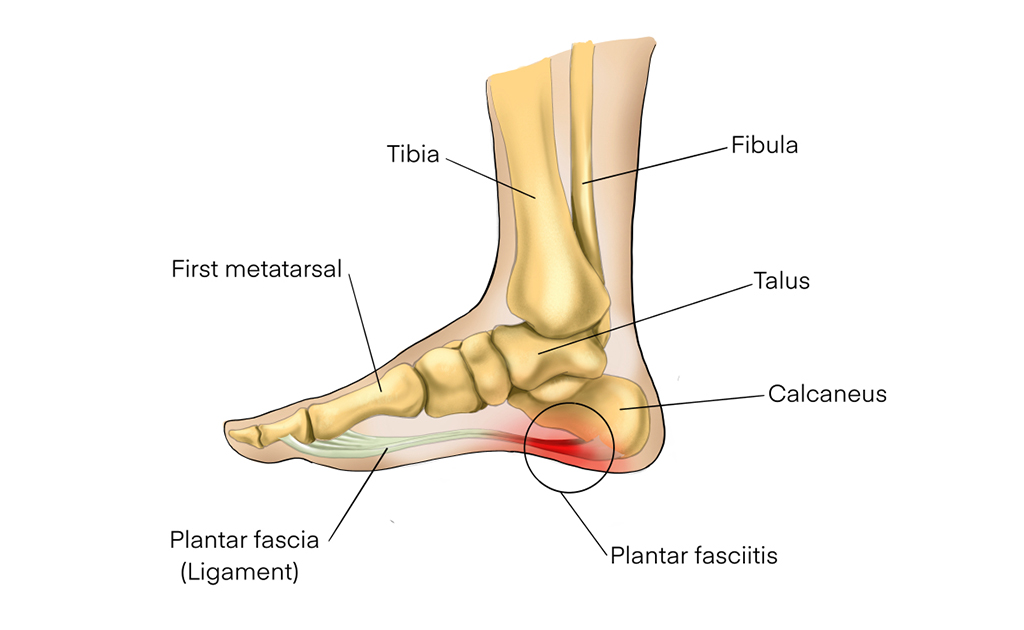

পায়ের গোড়ালিতে ব্যথা বা প্লান্টার ফ্যাসাইটিস থেকে পরিত্রাণের উপায় কী?

0 SHARES Share Tweet আপনার কি সকালে ঘুম থেকে ওঠার পর মেঝেতে পা ফেলার সময় ব্যথা লাগে? অথবা সারাদিনের কাজের পর রাতে পায়ের...